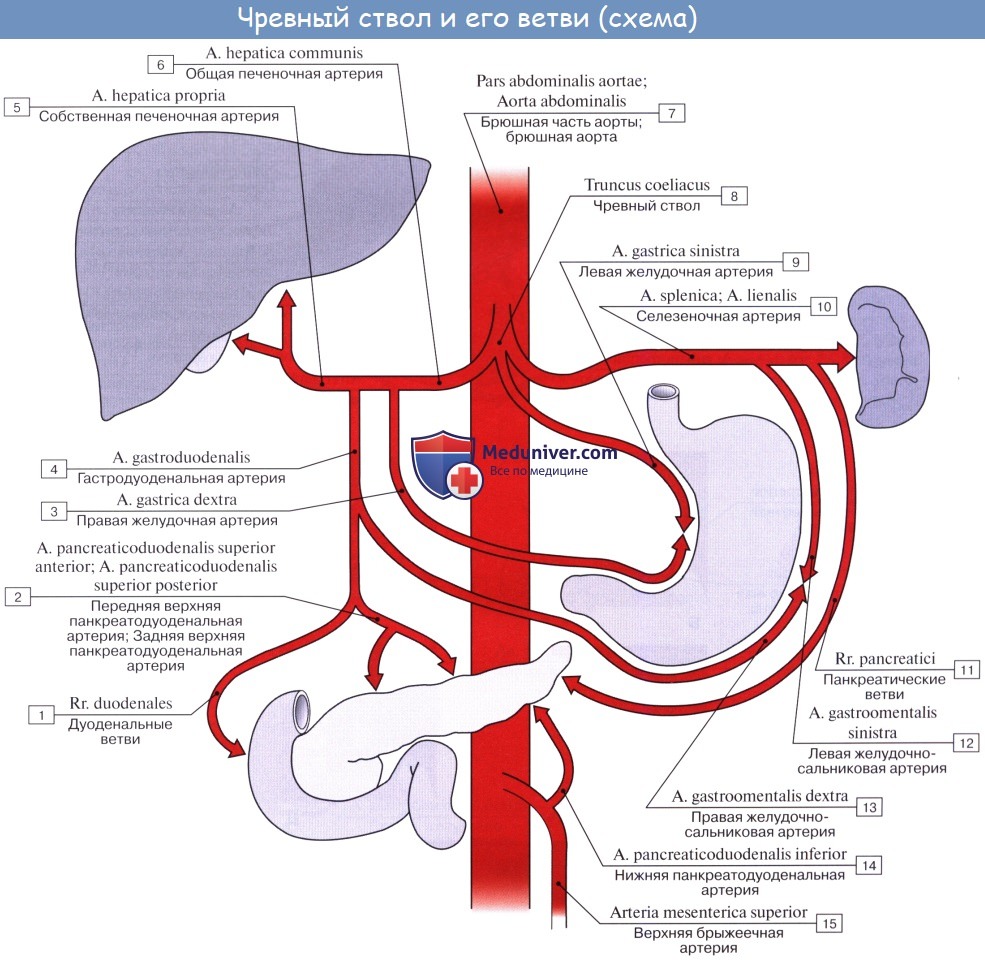

Нормальный диаметр корня аорты: медицинские нормы и отклонения